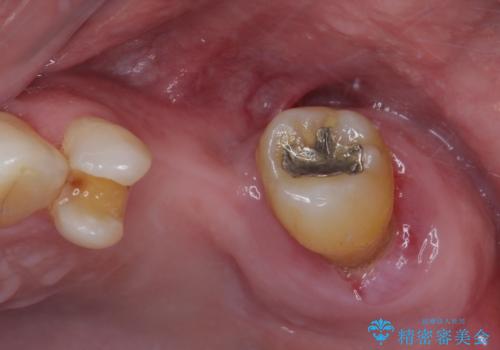

欠損の多い奥歯 インプラントによる補綴治療

- 地元ではなかなかインプラント治療を行ってくださる医院がないとのことで、転勤で東京にいる期間に治療を行いたいとのことで来院された患者様です。

上顎は左右ともに骨が少ない状態であり、特殊なドリルを用いた歯槽骨の拡大や自家骨挙上などを行いながらインプラントを埋入していくこととしました。

右下の銀歯も気になるとのことで、インプラント治療と並行してオールセラミックによるブリッジ補綴治療も行うこととしました。